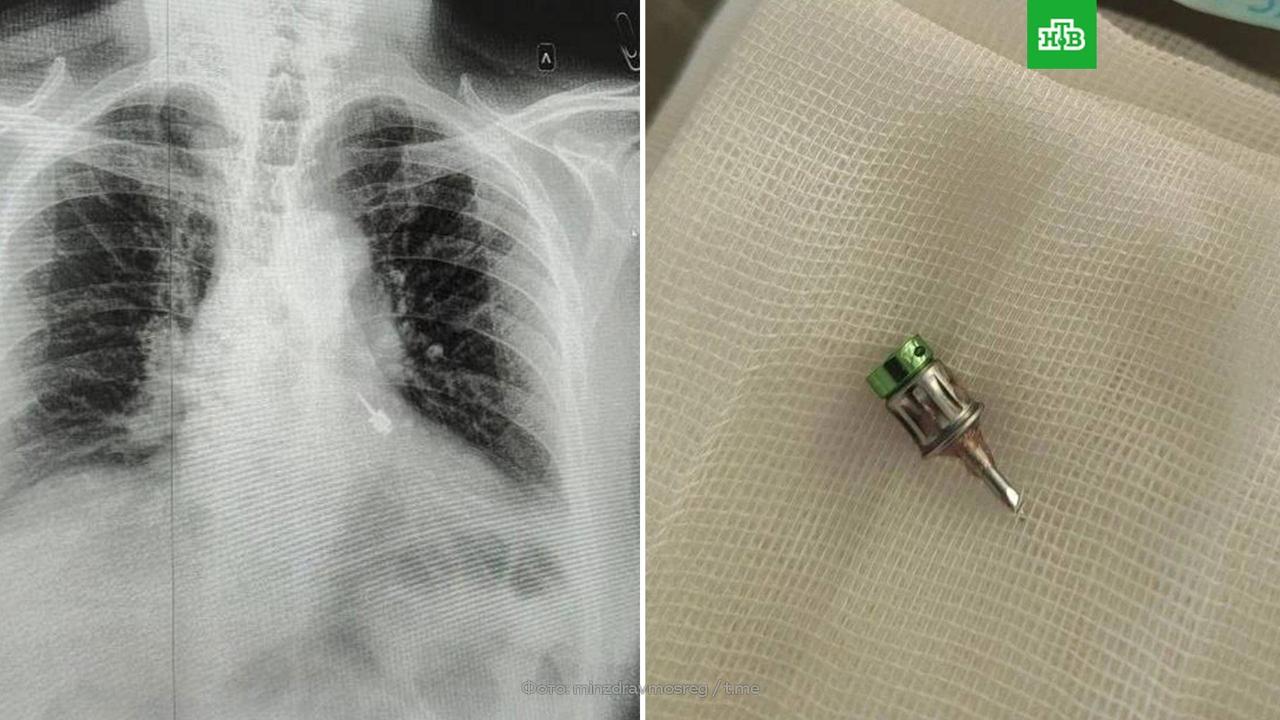

Новая фобия в копилку: стоматологический бор попал в бронхи жителю подмосковных Мытищ во время лечения зубов в частной клинике.

Мужчине экстренно сделали операцию. Врачи аккуратно достали бор, не повредив ткани дыхательных путей, поэтому через несколько дней пациент уже был дома.